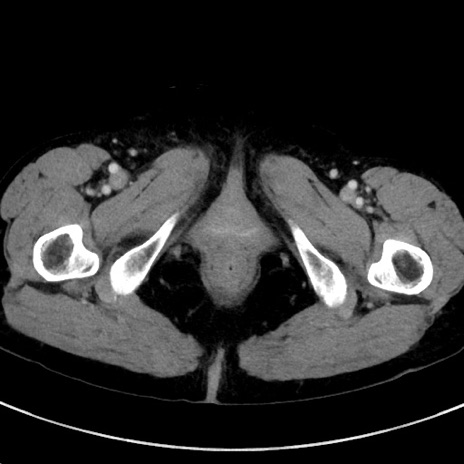

症例23(横断像)

【症例】70歳代女性

【主訴】下腹部痛・嘔吐

【現病歴】2日前より腹痛あり。昨日嘔吐あり。症状改善しないため来院。

【既往歴】胃GISTに対して胃部分切除後。

【身体所見】BT 37.1℃、BP 128/77mmHg、腹部:平坦・軟、下腹部に圧痛あり。

【データ】WBC 10200、CRP 0.31